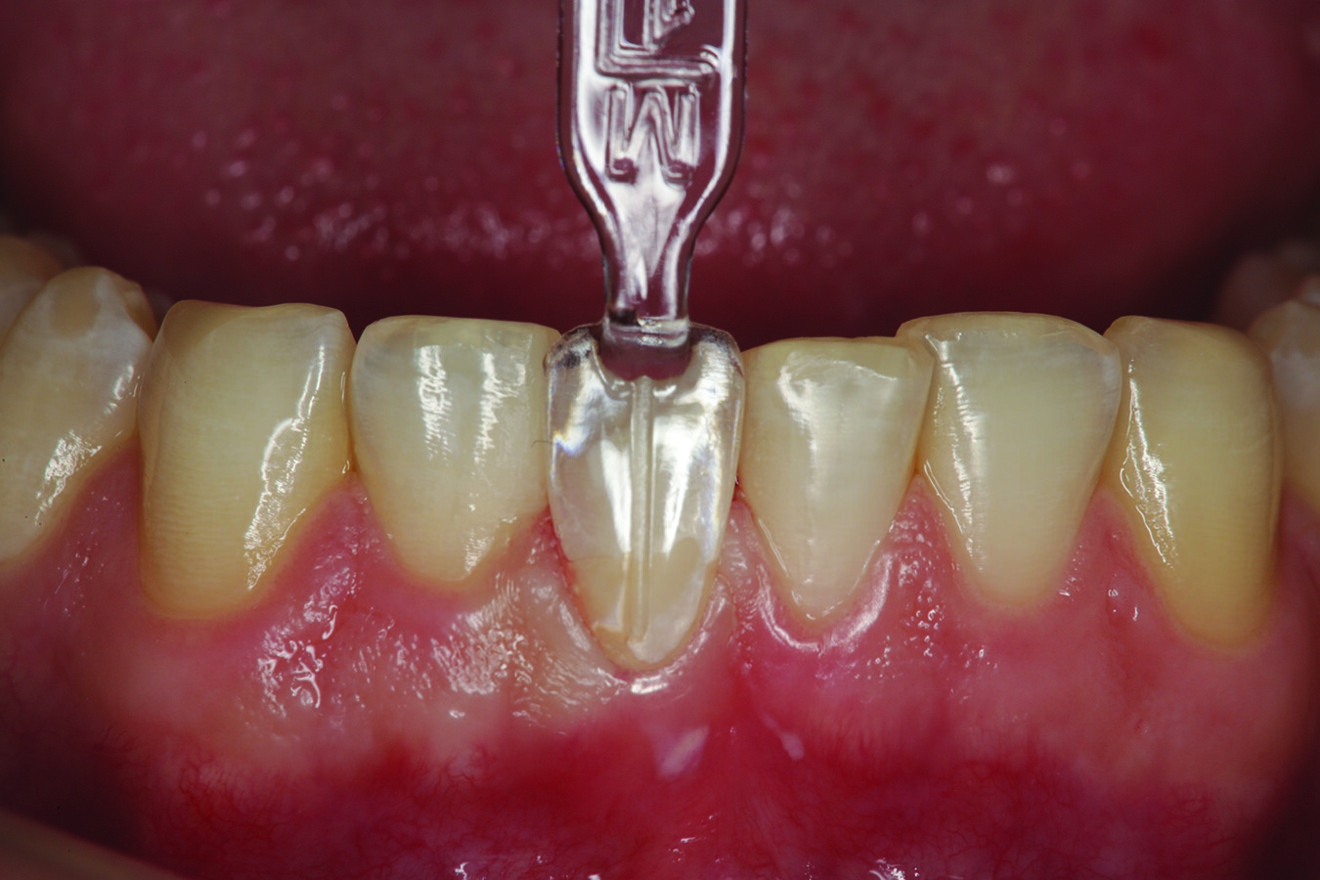

Fig. 1: Pre-op retracted facial view of the fractured composite restoration on tooth #11 with the teeth in maximum intercuspation. (All images: Robert A. Lowe)

The patient presented with a fractured Class IV mesial–incisal composite restoration on tooth #11 (Fig. 1). It had been repaired three times dur­ing the past year and had fractured again. Was this due to poor technique, maybe inferior materials? More than likely, it was due to occlusion. Aside from the amount of composite on the facial sur­face that extended beyond the fractured area, most of the palatal surface of the tooth was worn through to the dentine due to hyperfunction in protrusive and lateral excursion over many years, creating a functional and aes­thetic dilemma for the patient. A “conservative” approach may have been to bond the tooth again with composite and hope for the best. However, this may not have been the best long-term approach considering the functional stress in this area, even with the best tooth alignment. After all, how conservative is it to continually assault the tooth with rotary instrumentation to keep fixing a composite that continues to fracture?